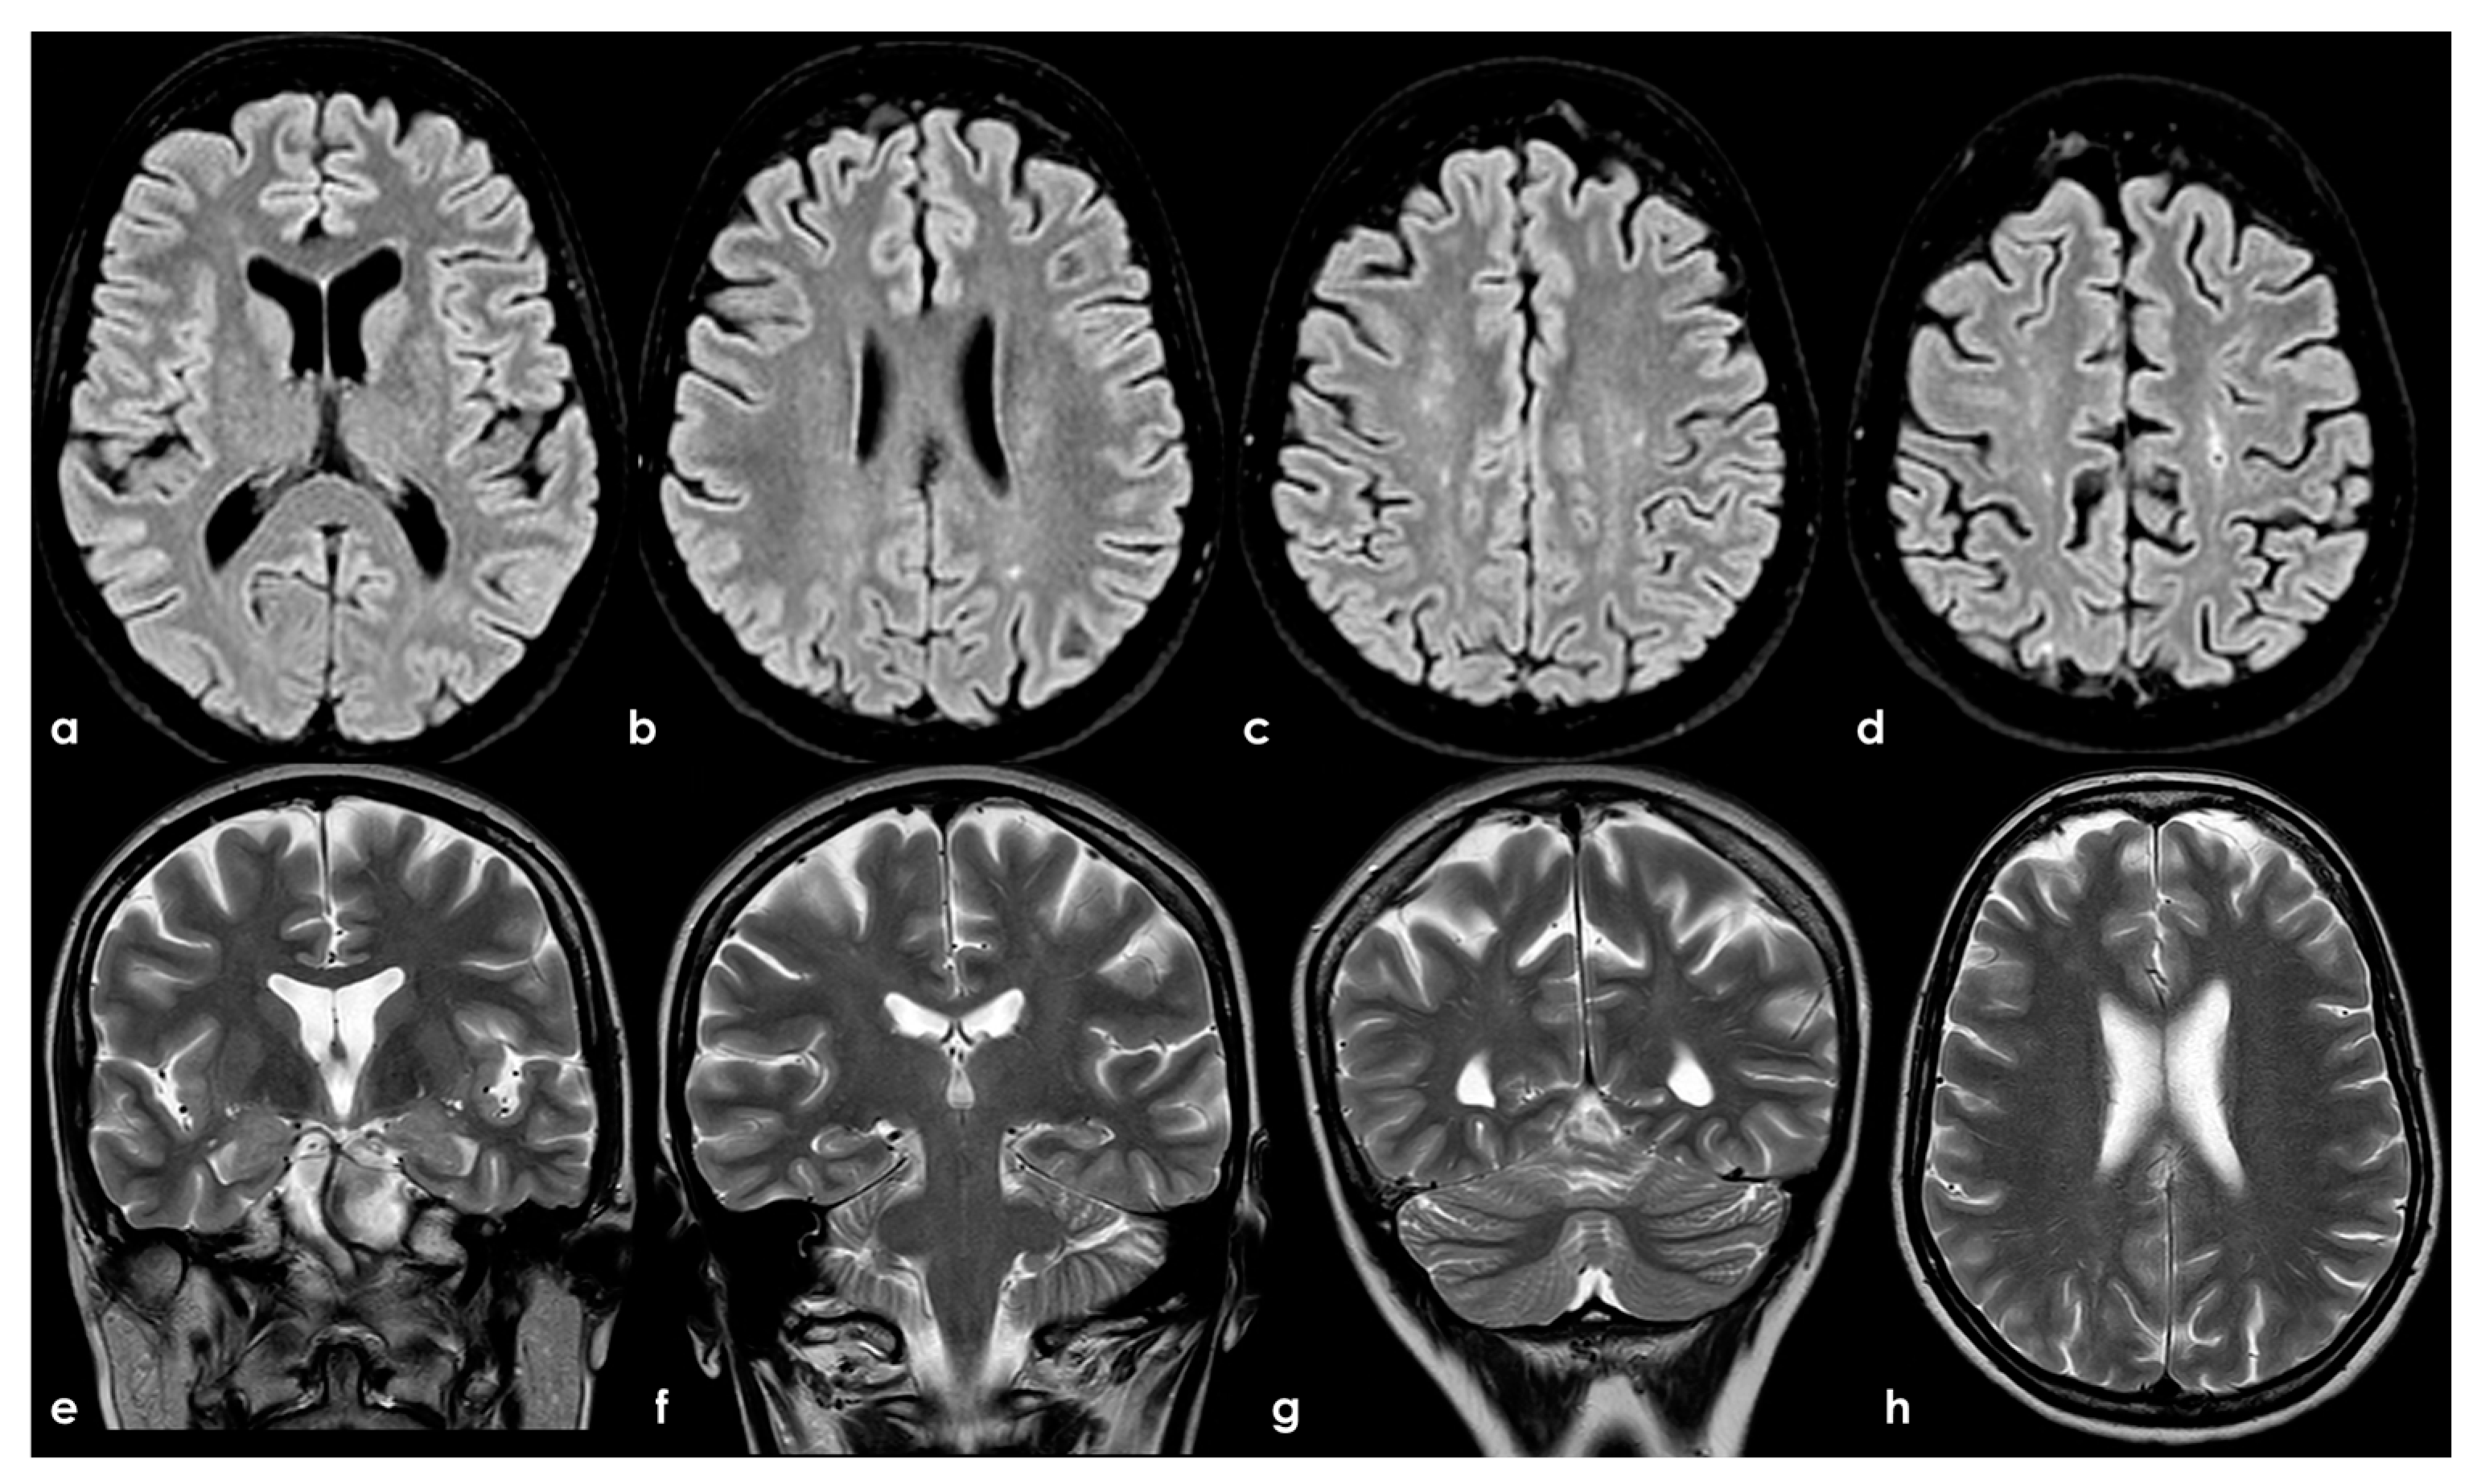

Brain MRI (axial FLAIR in panels (a–d), coronal T2W in panels (a–g), and axial T2W in panel (h)) showing small punctate white-matter hyperintensities in the centrum semiovale, with a trend to watershed distribution (panel (d)), and a mild increase in enlarged perivascular spaces in the subcortical white matter (panels (e–h)).

In the longitudinal evolution of neuroradiological patterns, SVD markers might appear, as in Figure 8 (same patient as in Figure 7 but 8 years later and without new clinical events on anticoagulant treatment).

Figure 8.

Brain MRI (axial FLAIR) at baseline (panels (a–c)) and after 8 years (panels (d-f)), showing the increase of WMHs in the subcortical white matter.